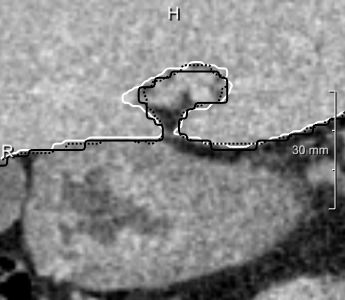

We observed some problems with narrow fissures and gaps (5 left, center), and hypothesized that reducing the resampling target voxel size from 2 mm to 1 mm isotropic could help here. We could not observe qualitative changes, and the volumetric overlap did not change significantly. The MICCAI scores, however, showed significant improvements (Wilcoxon ) due to reduced surface distances, at the expense of higher GPU memory requirements and longer training and classification times.

Lastly, we evaluated 3D U-nets, because slice-wise segmentation of volumetric images may lead to characteristic artifacts in general. However, both 3D U-nets performed significantly worse than the 2D ensembles. The 3D models performed better in some of the problematic areas of the 2D approaches (which were not many), but also brought new problems (5 right). We attribute this to the limits imposed by the available GPU memory on training batch sizes (2). U-nets with four resolution levels need 44 voxels of padding on each side, and when naively going from 2D to 3D (without reducing the number of filters [11, 12]), 8 GiB of memory are just enough to train with mini batches containing a single patch of 20³ voxels each, which does not suffice for stochastic gradient estimates stable enough for convergence. The ratio between the number of output voxels the loss is computed on and the number of input voxels after padding is given in the last column of 2. Consequently, the U-net performed significantly better than the 3D U-net with unpadded convolutions (Wilcoxon ).